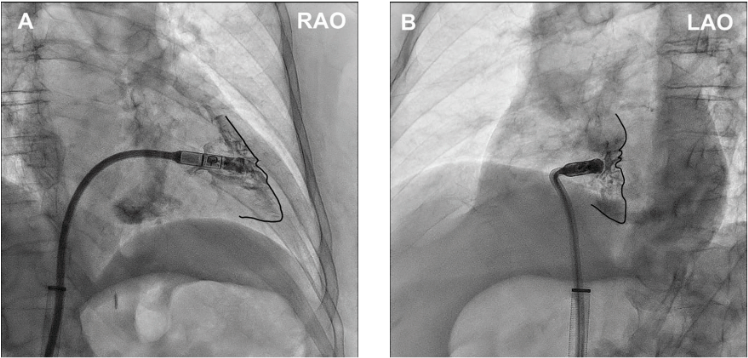

Case 3. A 77-year-old obese male with a past medical history of diabetes, peripheral venous disease, and AF presented after a syncopal event at home, with an unknown down time of approximately 6 hours. When he awoke and was able to contact emergency medical services, he was brought to the ED with a heart rate of 30 beats per minute in AF with complete heart block and left bundle branch escape, which subsequently developed into slow ventricular response with longest RR interval of 7.7 seconds and right bundle branch escape. The patient was taken for leadless pacemaker implantation with the AVEIR VR leadless pacemaker (Figure 3).

Li et al. Right Ventriculography Improves the Accuracy of Leadless Pacemaker Implantation in Right Ventricular Mid-septum. Reproduced with permission under CC BY 4.0. creativecommons.org/licenses/by/4.0/.15